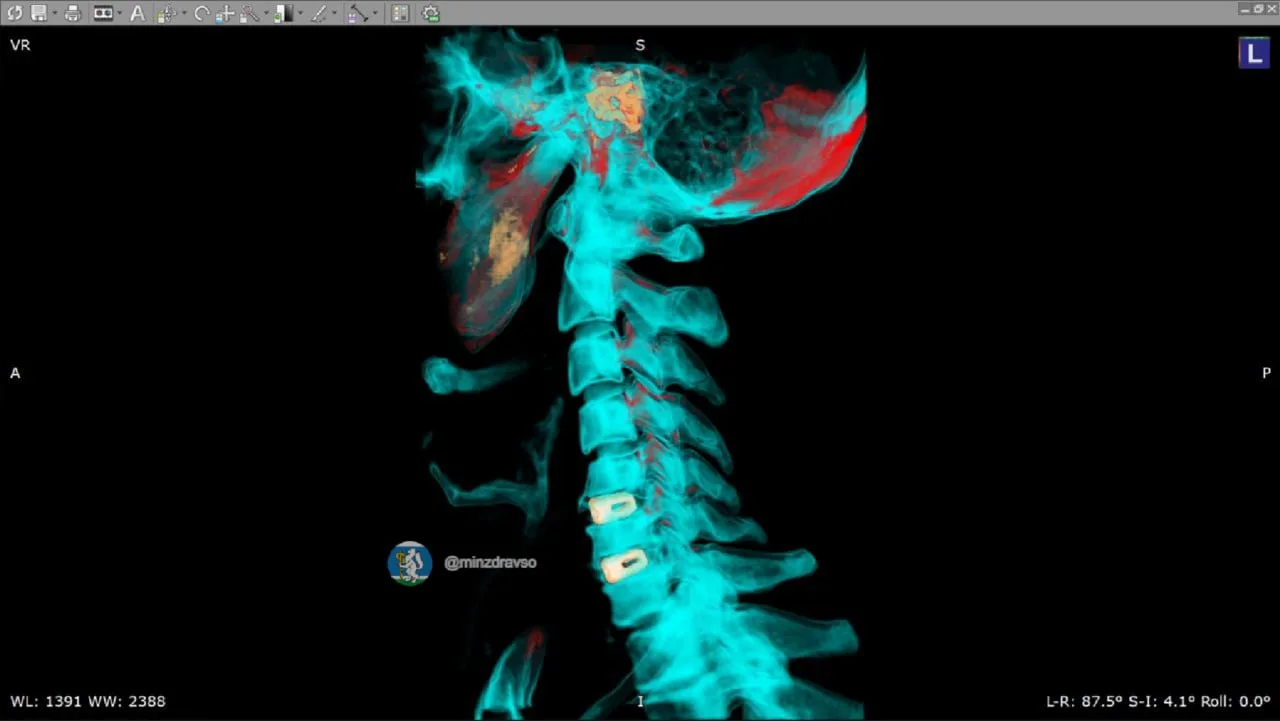

🦴 Точность до миллиметра: как уральские онкологи возвращают полноценную жизнь после сложных диагнозов

Онкоортопедия — одно из самых сложных направлений в медицине. Здесь нельзя допустить ошибку: на кону не просто удаление опухоли, а возможность человека снова ходить, работать, жить полноценно. В Свердловском онкологическом диспансере развивается передовая технология, которая меняет правила игры: замена поражённых костных сегментов высокоточными индивидуальными имплантами.

🤖В настоящее время для пациентов моделируют индивидуальные импланты, которые затем изготавливают на производстве. С 2024 года профильные специалисты учреждения здравоохранения выполнили пять вмешательств с полным замещением имплантом удалённой костной ткани.

Одним из недавних подобных случаев стало выявление новообразования у свердловчанки спровоцировало патологический перелом бедренной кости при обычной домашней нагрузке. После углублённой диагностики было принято решение провести органосохраняющую операцию, в ходе которой 20 сантиметров поражённой кости заменили индивидуальным титановым эндопротезом, смоделированным медиками на основе послойной компьютерной томографии и отпечатанным на заводе.

(на нашем фото)

🔥После успешной операции, которая длилась 5,5 часов, пациентка находится в раннем реабилитационном периоде и, несмотря на сложность и обширный объём хирургического вмешательства, передвигается самостоятельно.